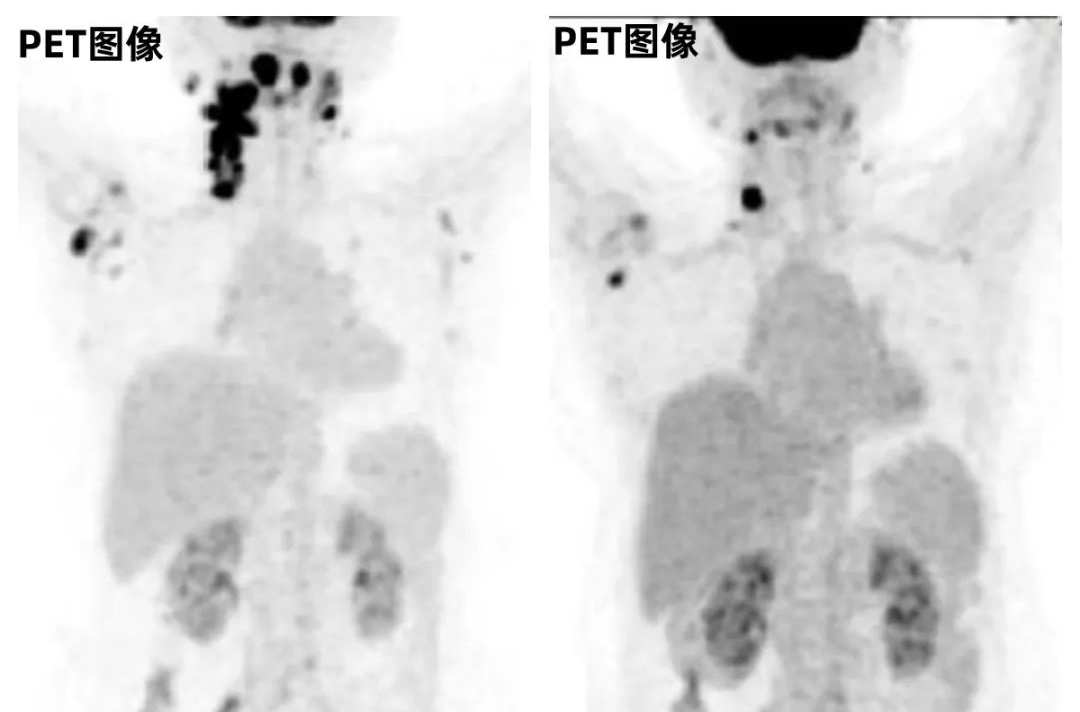

近日,ImmunityBio公布了一种现成的同种异体CD19嵌合抗原受体自然杀伤细胞疗法(CAR-NK)的QUILT-106临床研究(NCT06334991)的更新数据:数据显示持续完全缓解,缓解持续时间已延长至15个月且仍在持续,至今观察到100%的疾病控制。

1月16日,ImmunityBio公布了正在进行的QUILT-106临床研究(试验编号NCT06334991)的最新疗效与安全性数据。该研究评估的是一种现成型同种异体CD19嵌合抗原受体自然杀伤细胞疗法。该CD19 t-haNK疗法是一种靶向高亲和力自然杀伤细胞疗法,通过基因工程改造表达CD19特异性嵌合抗原受体,联合...